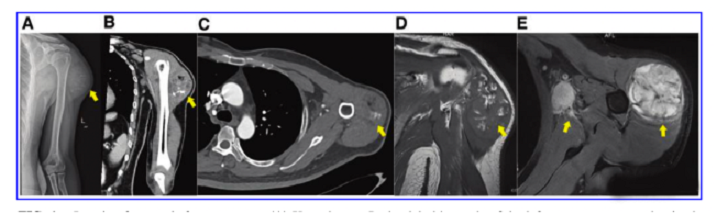

接受iPS細胞治療患者的畸胎瘤。(A) 在左上臂的三角肌中,觀察到一個圓形的混合密度腫塊,邊界不清,為9.6±5.2cm。(B) CT冠狀掃描顯示三角肌內(nèi)有一圓形混合密度腫塊,邊界不清。(C)增強CT軸向掃描顯示不均勻和中度強化。(D)MRI T1W以等信號為主,有不規(guī)則的高低信號區(qū)。(E) T2W也顯示高信號和斑片狀低信號區(qū),左腋窩有多個淋巴結(jié)腫大。